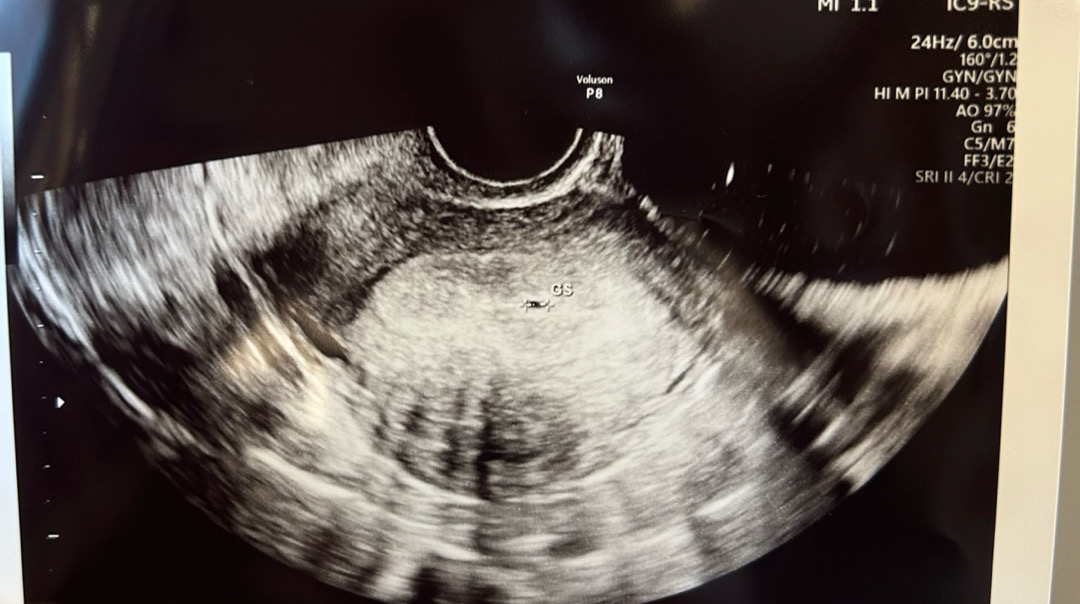

12/9 마지막 생리 시작일 1/5 첫 임테기 두줄 확인 1/8 아기집 아주 조그맣게 확인 피검사하러 병원에 갔다가 제가 생리 주기가 28-30일로 규칙적인 편이라고 말씀 드리니 초음파로 아기집 보일 수도 있다고 하셔서 피검사 스킵하고 바로 초음파를 했고, 0.3센치 아기집을 확인했어요❣️ 의사쌤은 아직 확실한 건 아니지만 4주차 크기에 해당하고 위치도 아기집 위치라 임신 맞을 거 같다고 하시네요 ㅎㅎ 다음주에 한 번 더 초음파 보기로 했습니다. 2월 3월 해외여행 예정이었는데 전부 취소하고 난리였네요 ㅋㅋ 무사히 쑥쑥 커줬으면 좋겠어요!!